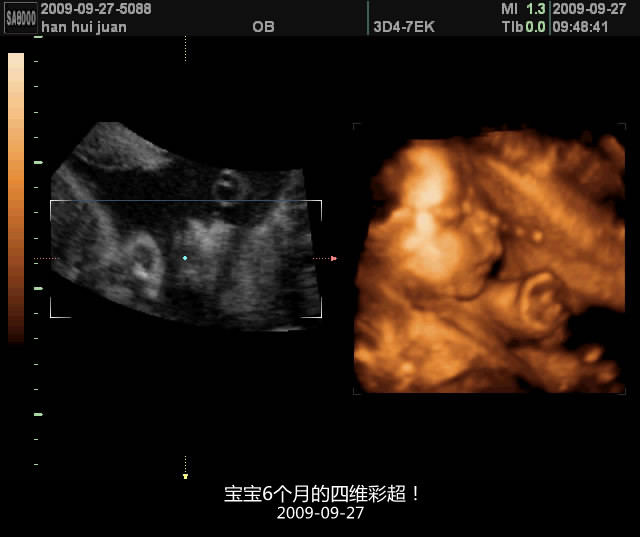

就这样宝宝在我肚里健康地成长着,再没有吓我们 在她6个多月的时候我迫不及待地想看看她什么样子 于是订了四维彩超和孕妇照 那时候正赶上闹甲流呢,可是订金交了,又不得不去 照了两次第一次宝宝不配合总是看不到正脸 说到这里还有个小插曲 照的时候医生照到宝宝隐私的部位,我当时一看,恩? 多出来一块儿 回来那个郁闷啊 以为是个男孩,要知道我是特别特别喜欢小女孩的 老公虽然内心欣喜但是还是装模作样的安慰我 男孩就男孩…… 结果生下来一看,是女孩!惊喜啊! 宝宝出生后我看了看下面,原来她太瘦了,所以下面两边的肉肉没包住啊,才看见中间突出一块儿 闹了个大笑话! 不知怎么的,当时看到这个照片觉得宝宝特别可爱 虽然别人都说跟外星人似的,可是自己就是怎么也看不够。 那时候的我也胖的不像样子了,这还不是最胖的呢。我孕期共长了40多斤 但宝宝生下来却只有5斤9两,惭愧啊!